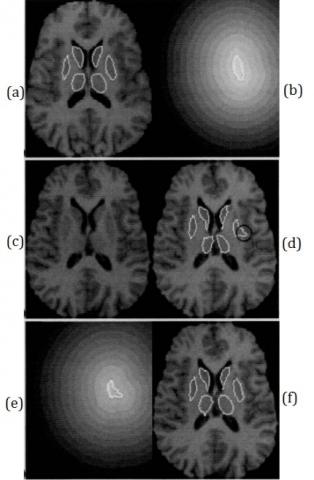

In order to more clearly compare the segmentation performance of different algorithms, Figure 5 shows a set of 2D views of experimental results.

Figure 5. Comparison segmentation results between Demons nor-rigid algorithm and the proposed algorithm

Figure 5 (d) gives the segmentation result of the left putamen. It is only registered with the gray similarity degree registration, and examines the position of the black circle in the picture. Obviously, the result is not ideal. Therefore, if we consider only the gray-scale similarity, it is very likely to fall into the local optimal solution. Figure 5 (e) is a distance map of the deformed left putamen. It can be seen that the shape of the left putamen after deformation is quite different from that of the original shape. Then the shape of the left putamen in the source image is similar to the shape of the left putamen in the target image, and the segmentation result is better under the combined effect of the gray similarity and the shape similarity.